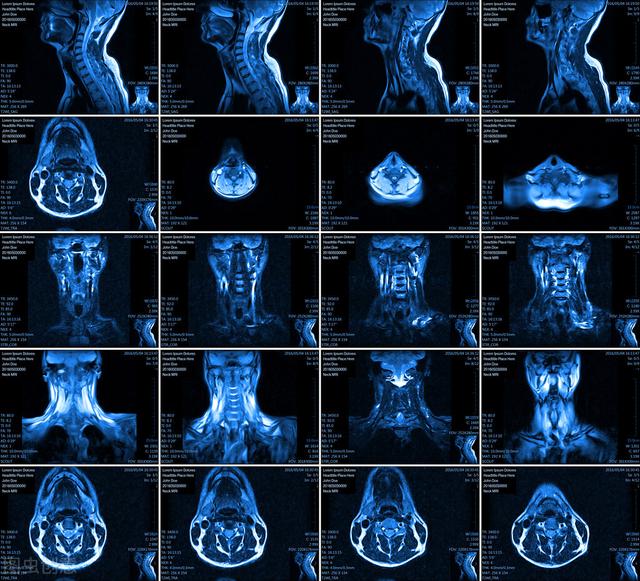

- MR-磁気共鳴検査とも呼ばれ、主に周囲の軟部組織、筋肉、脊髄、神経、血管を映し出すことができ、病変をより明瞭に示すことができ、病変の性質を判断し、比較的小さな病変を発見することができる。